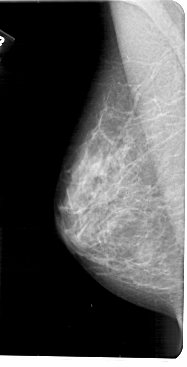

A_1835_1.RIGHT_MLO

RIGHT_MLO LINES 5431 PIXELS_PER_LINE 2491 BITS_PER_PIXEL 12 RESOLUTION 43.5 OVERLAY